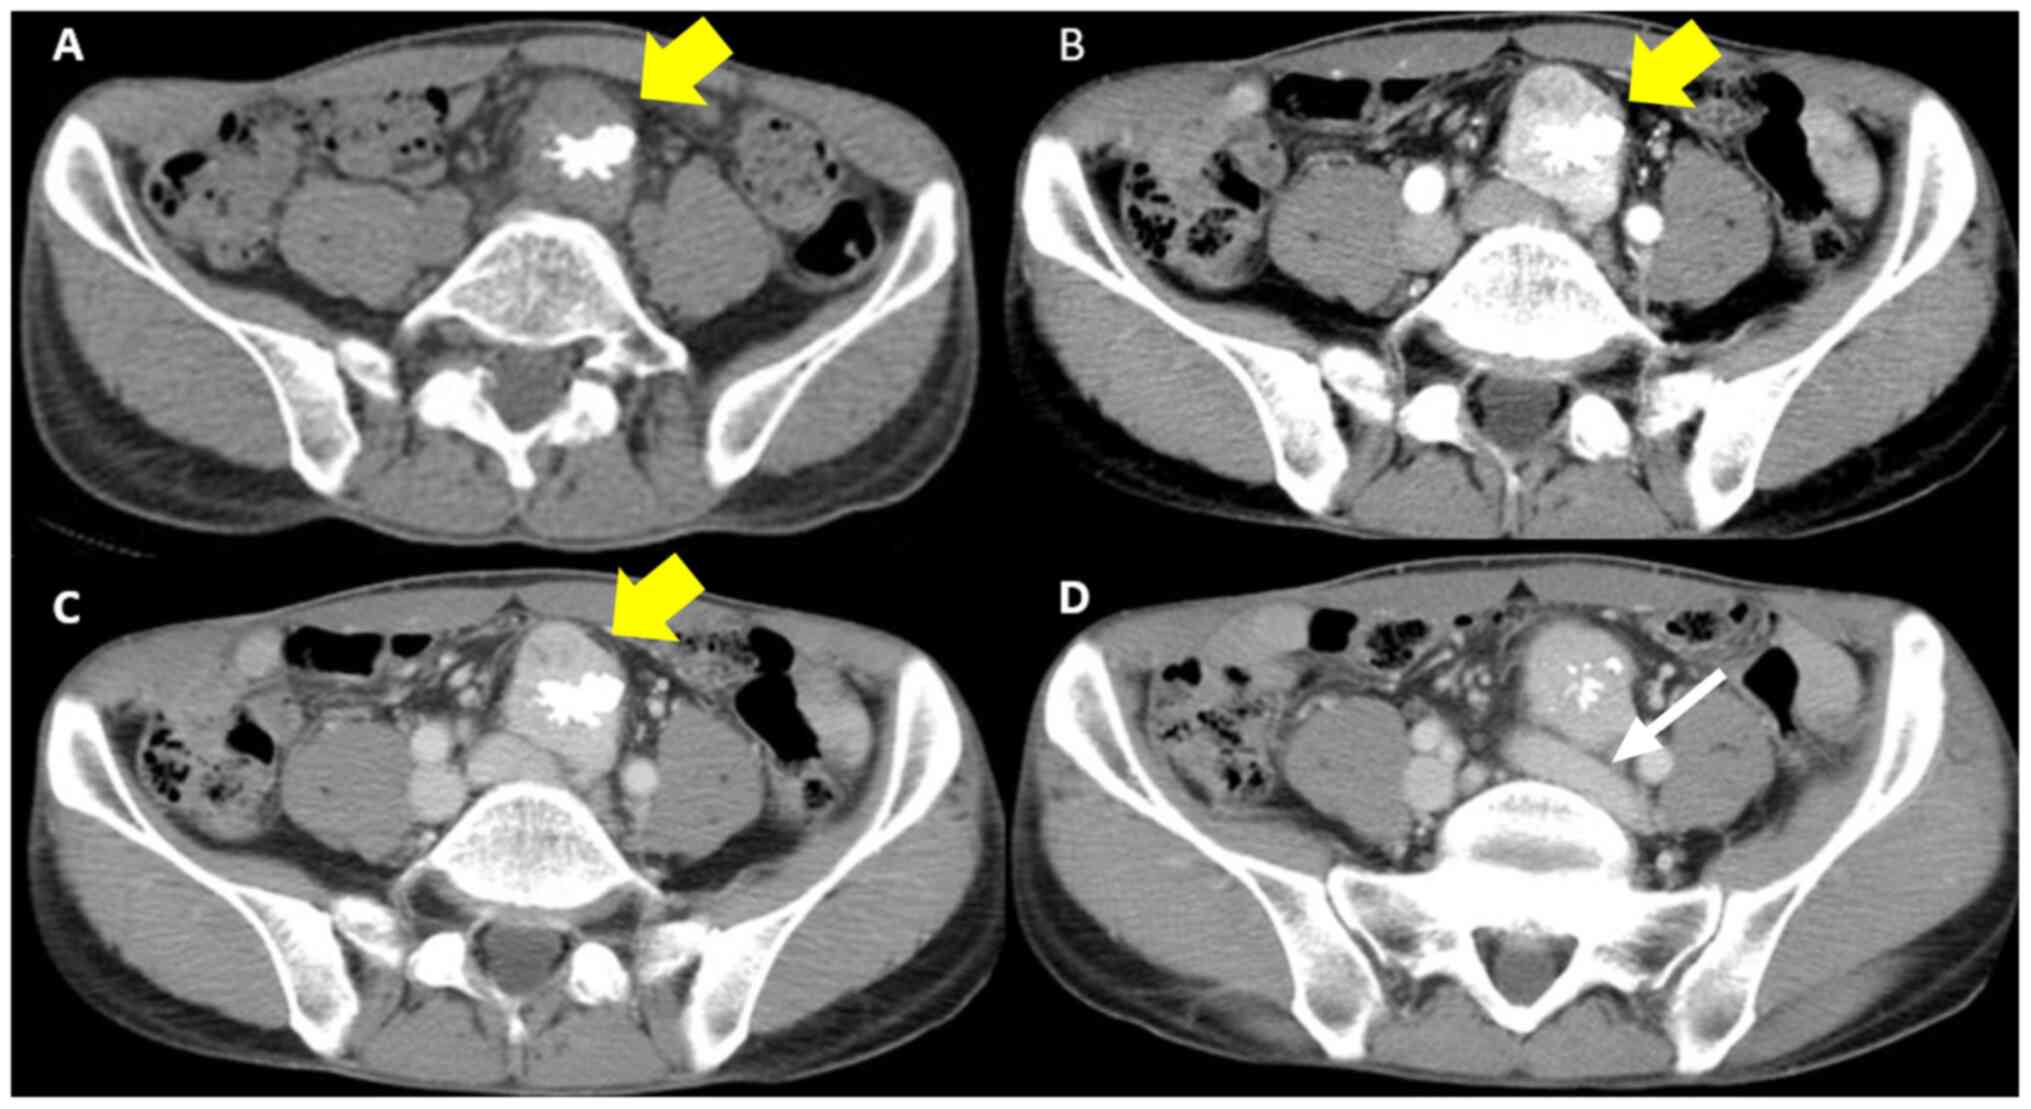

A 44-year-old man presented with a history of diarrhea at another hospital. He was diagnosed with acute enteritis with computed tomography (CT), and the diarrhea was relieved after a few days. The CT scan incidentally revealed a pelvic retroperitoneal mass with calcification, and he was referred to Osaka University Hospital. The patient underwent appendectomy for appendicitis 30 years ago, and had no viral infection or history of any other diseases. The pelvic calcification was previously identified in previous abdominal X-rays, but further examination was not performed. Physical examination revealed no abnormal symptoms. Laboratory blood tests, including for tumor makers (CA19-9 and carcinoembryonic antigen) were normal. Any abnormal finding was not detected by colonoscopy. The abdominal contrast-enhanced CT scan revealed a well-defined 50x30 mm mass behind the sigmoid mesenteric, under the bifurcation of the aorta in the pelvic retroperitoneal. Non-enhanced phase imaging revealed coarse calcification inside the mass, and evident contrast enhancement was observed in the mass during the arterial phase (Fig. 1). Magnetic resonance imaging (MRI) also revealed a well-defined 50x30 mm solid mass situated in the pelvic retroperitoneal. The mass demonstrated heterogeneous and moderately hyperintense signal intensity, and the low signal intensity corresponded to calcification in the T2-weighed images and diffusion-weighted images (Fig. 2). A positive emission tomography/CT scan was performed to exclude the possibility of paraneoplastic manifestations of a primary tumor, and it revealed a 50x30 mm space-occupying lesion with hypermetabolic activity (SUVmax at 4.1) (Fig. 3). Possible differential diagnosis based on the images were CD, primary mesenteric gastrointestinal stromal tumor or leiomyoma. At first, a diagnosis of CD was doubted as the tumor had calcification, exhibited a strong contrast in imaging, had an uniform edge and a relatively uniform inside on the abdominal CT scan; the tumor was generally isointense on T1 weighted images and hyperintense on T2 images (8). Surgical resection following embolization was suggested. Angiographically, the tumor was hypervascular with a dense capillary blush, and it was supplied by the middle sacral artery (Fig. 4). The vasculature of the mass was embolized by DMSO and the patient was operated on the following day.

Abdominal and pelvic contrast-enhanced CT findings. (A) CT scan in the non-enhanced phase. The yellow arrow shows the 50x30 mm, well-defined mass with calcification under the bifurcation of the aorta in pelvic retroperitoneal. (B) CT scan in the arterial phase. The imaging revealed an evident contrast enhancement mass. (C and D) CT scan in the venous phase. The white arrow shows the mass is close to left common iliac vein. CT, computed tomography.